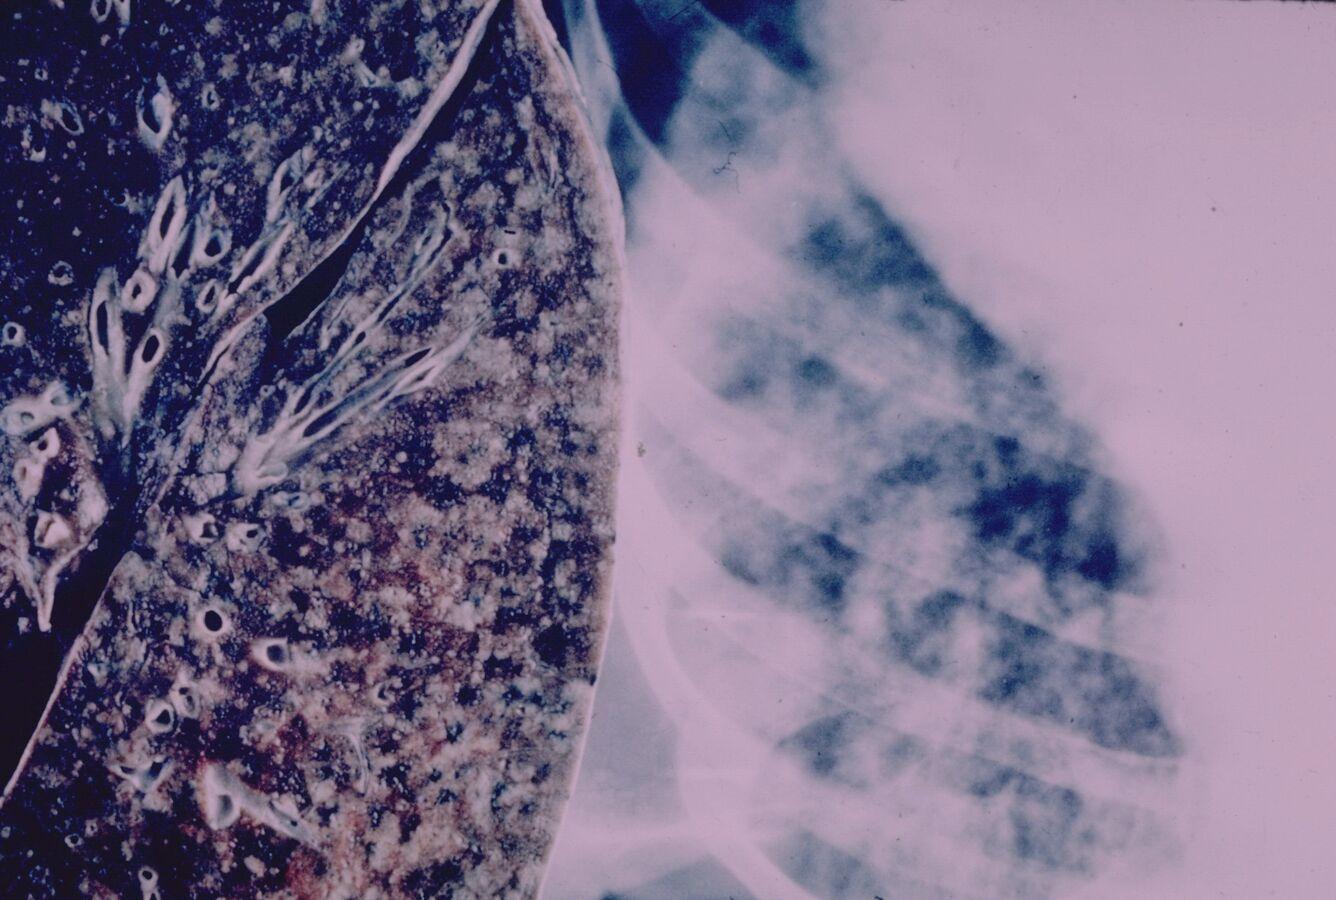

وذكرت “الصحة العالمية” أن السل مرض قابل للوقاية والعلاج، وينتشر عبر الهواء عند سعال المرضى أو عطسهم.

وفي ما يتعلق بالابتكار الطبي، فقد أشار تقرير منظمة الصحة العالمية السنوي إلى أنه يجري حاليا تطوير 63 اختبارا تشخيصيا، و29 دواء جديدا، إلى جانب اختبار 18 لقاحا تجريبيا على البشر، بينها 6 في المرحلة الثالثة، ورغم مرور أكثر من قرن على استخدام لقاح “BCG” للأطفال، فإنه لا تزال اللقاحات المخصصة للبالغين غائبة.